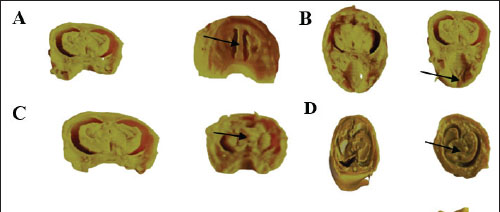

Fetal visceral malformations

The visceral observations are presented in Table 4 and Figure 3. No visceral malformations were recorded in the fetuses of the control and vit C groups, except for one fetus that exhibited a palate and cerebral ventricle. Exposure of dams to 1/10 and 1/20 of THM LD50 resulted in various malformations in the palate, cerebral ventricle, cerebrum, liver, kidney, bladder, and ureter of the examined fetuses. The recorded visceral malformations were reduced in the groups treated orally with 1/10 and 1/20 of THM LD50 combined with vit C compared with the control and vit C groups.

Fig. 3. Cross and longitudinal sections of the head of a rat fetus. A. Cerebral ventricle, B. Palate. C. The cerebral hemispheres were unequal in size (asymmetric) in the head. D. Hypoplasia of the liver. E. Hypoplasia of the kidney, distends the urinary bladder with urine and dilated ureter (hydro ureter). (Control group at the left).